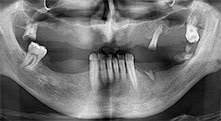

Bratu: Wir nutzen die Instrumente routinemäßig für die Entnahme von Knochenblöcken und das Spalten von Kieferkämmen. Weiterhin osteotomieren wir mit den Piezomed B6/B7 retinierte Zähne und entfernen nicht erhaltungsfähige Implantate. Alles Indikationen, bei denen es auf tiefe, saubere Schnitte ankommt.

Bratu: Wir bevorzugen Knochenentnahmen von der Linea obliqua externa des posterioren Unterkiefers, nicht aus der interforaminalen Region. Nach der Weichgewebsinzision verwenden wir die neuen Sägen, um den Umfang der Knochenentnahme zu definieren. Wir erledigen damit in fast 80 Prozent der Fälle auch die gesamte Präparation. Zusätzlich verwenden wir eventuell andere Piezo-Instrumente und zuletzt einen Meißel, um den Block zu mobilisieren. Das ist für uns eine sehr effektive Operationstechnik.

Bratu: Wir augmentieren im seitlichen Unterkiefer gern mit der Sandwich-Technik. Dabei wird ein Knochendeckel mit der Piezosäge präpariert und das krestale Fragment mit Mikroschrauben fixiert. Dazwischen platzieren wir eine Mischung aus autologem Knochen und xenogenem Knochenersatzmaterial. Das funktioniert sehr zuverlässig. Bei Kieferkammspaltungen im Unterkiefer sollten Sie nie auf ausreichend dimensionierte vertikale Schnitte verzichten. Sonst kann der Knochen leicht frakturieren.